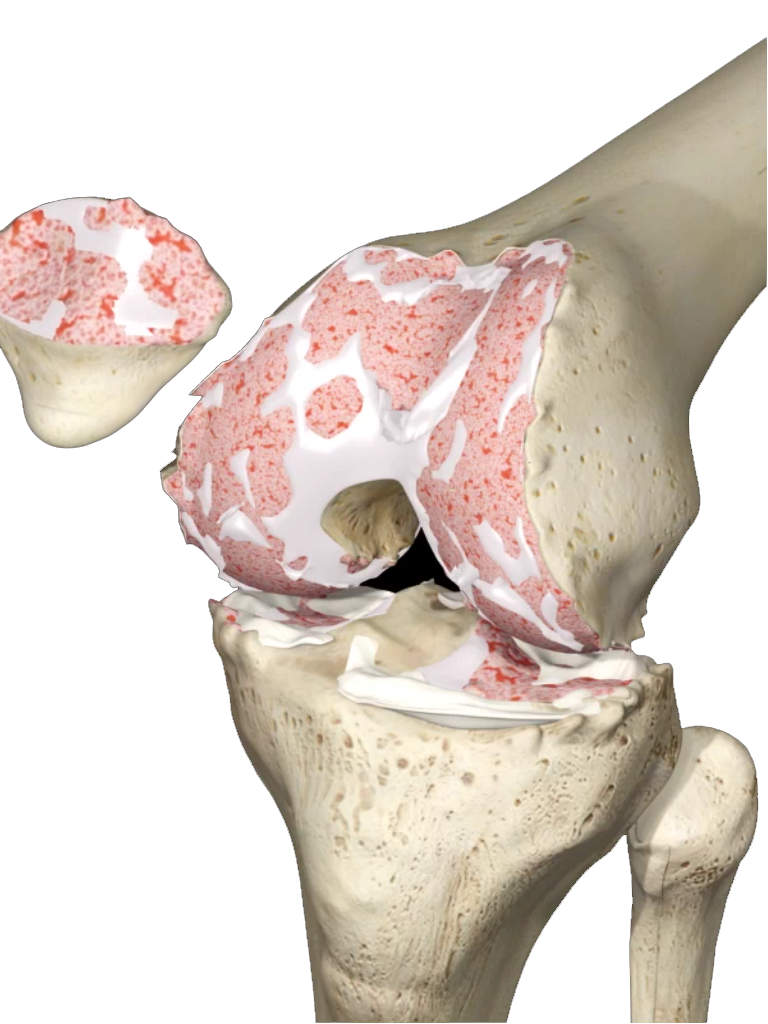

Actualmente la lesión de Ligamento Cruzado Anterior (LCA) ya no implica un problema su reparación y aún en deportistas de alto rendimiento pueden retornar a su alto nivel deportivo. La cirugía sin embargo, requiere de alta precisión para su éxito, por lo que requiere de una alta experiencia por parte del cirujano ortopedista. El procedimiento se realiza por tres incisiones, dos de 4 mm y una de 1 a 2.5 cm, por una de las incisiones menores se introduce la cámara con la que se revisa toda la articulación, por otra de las pequeñas incisiones se introducen los instrumentos necesarios y por la tercera se obtiene y se tuneliza el nuevo ligamento.

Cuando hay una ruptura de ligamento este hay que reemplazarlo de dos formas, ya sea utilizando un tendón de banco de tejidos o un tendón del mismo paciente que se obtiene de la misma rodilla lesionada. La ventaja de reemplazar el ligamento cruzado por injerto de banco de tejido es que la cirugía resulta un poco menos dolorosa y más rápida que hace que la rehabilitación sea más rápida.